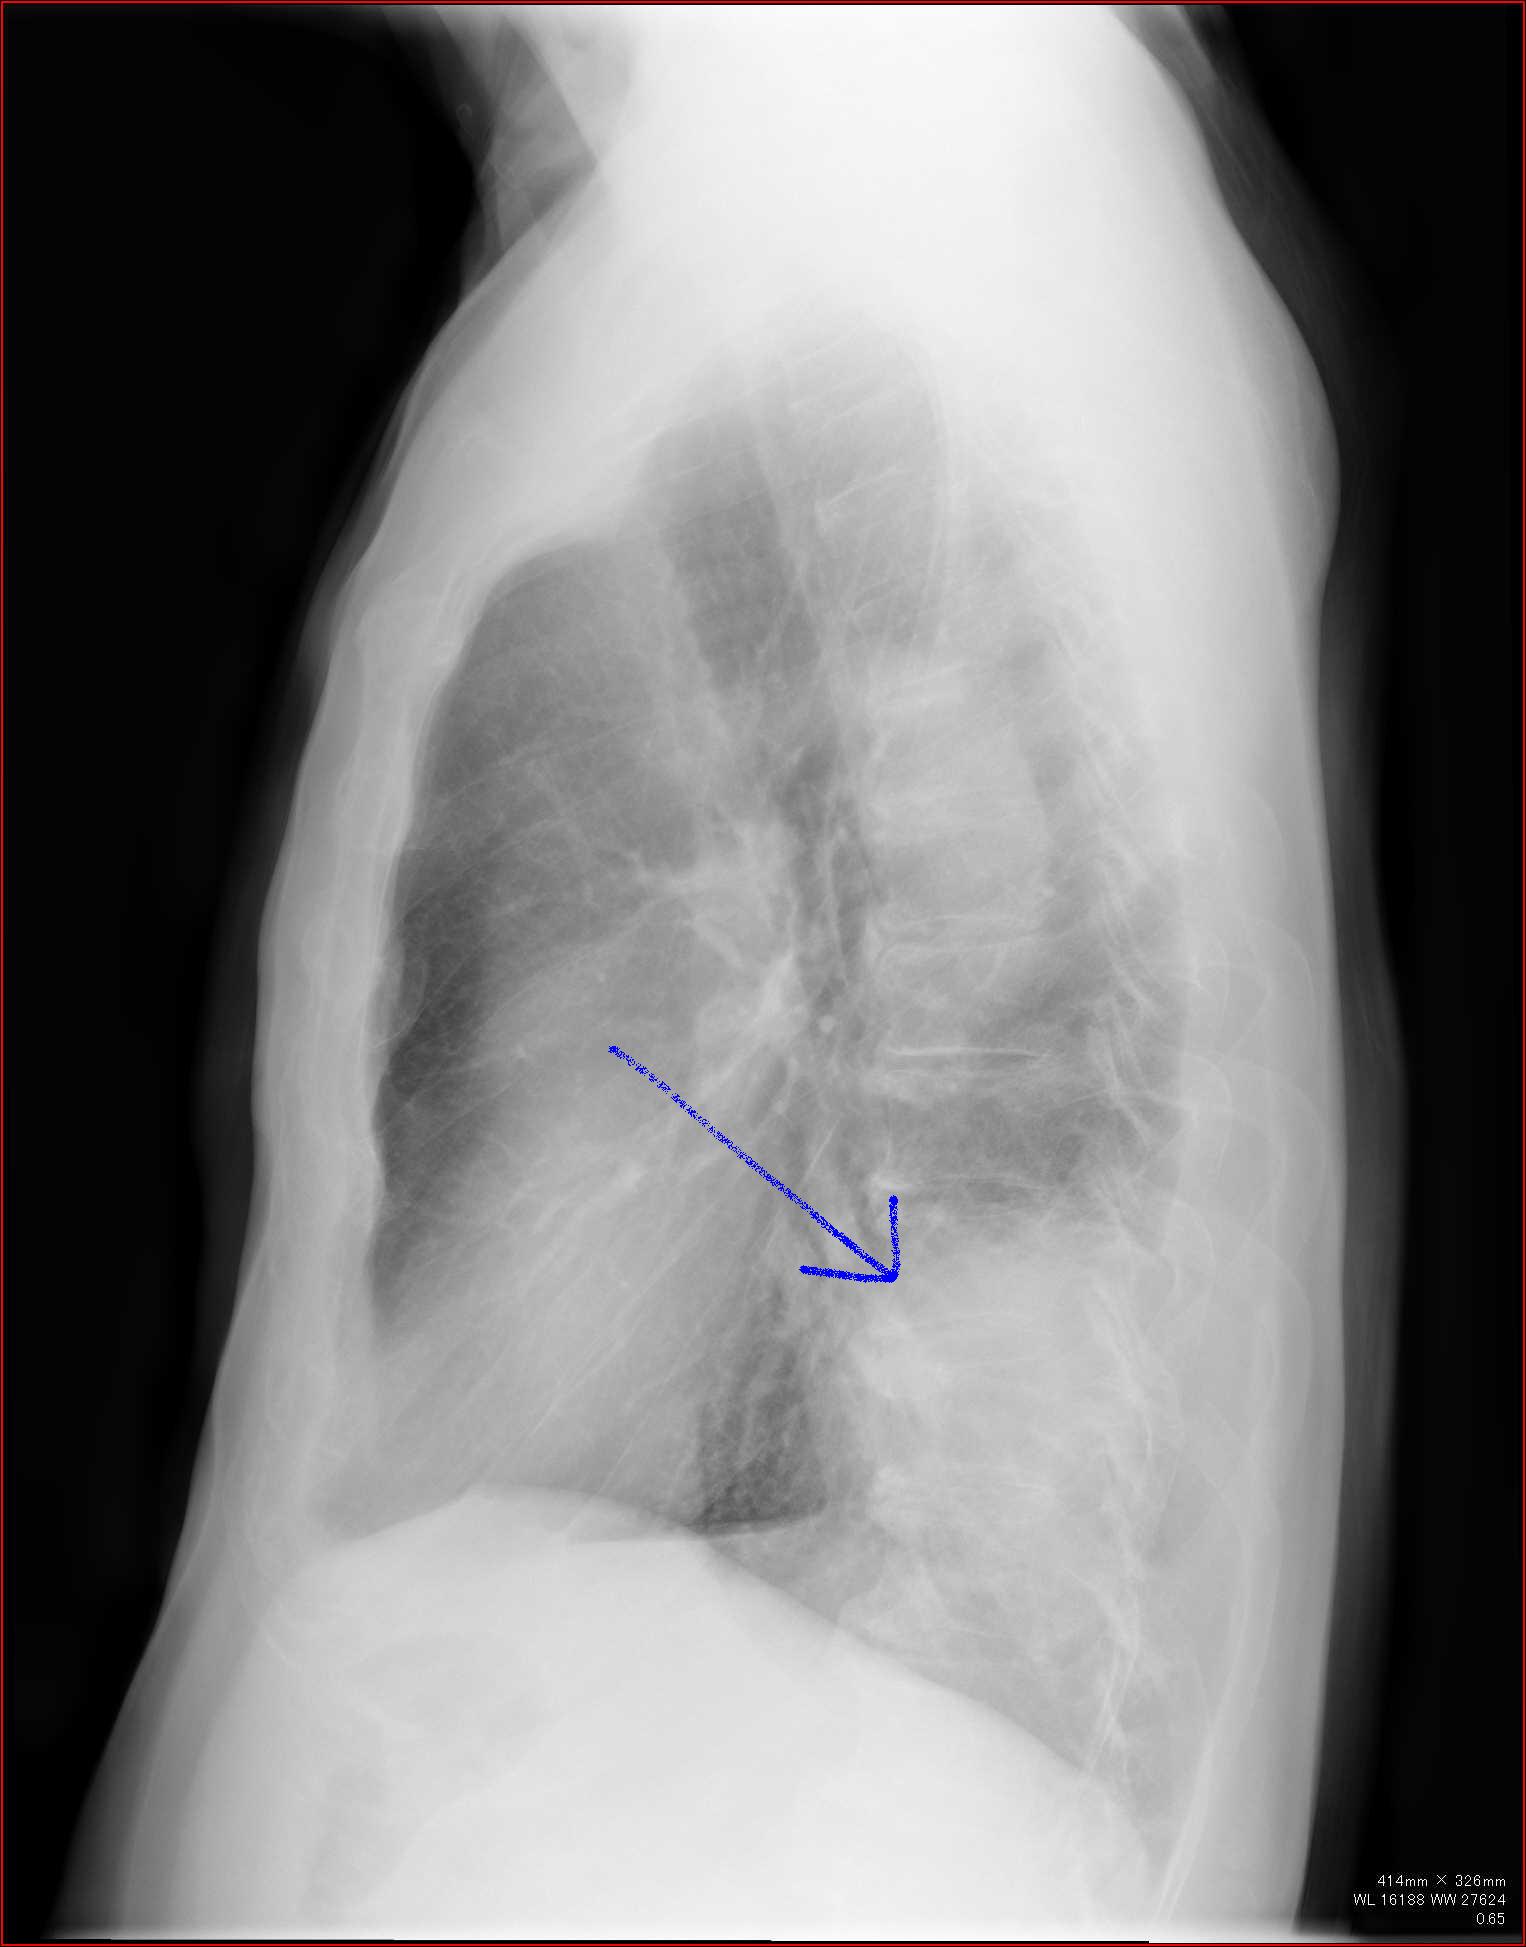

Aシルエット・サインを使う

陰影があったときに、果たしてその陰影はどこにあるのか。

上、中、下肺野のどこにあるかとともに、シルエット・サインをうまく使うことでどのセグメント(

1〜10に分かれている、例のやつ)を絞り込むことができます。